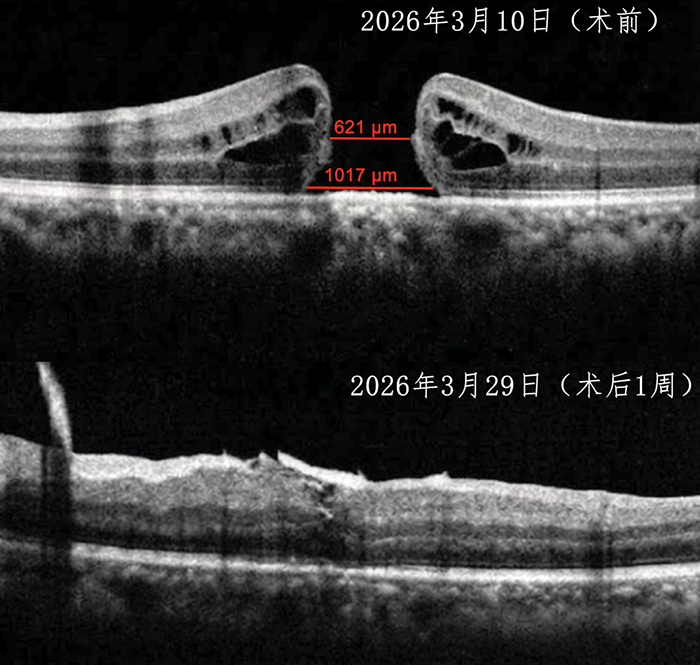

接诊后,中山一院贵州医院(贵医附院贵安院区)眼科团队立即为伍先生开展了全面细致的眼部检查。检查结果显示,其左眼视力仅为0.1,OCT影像清晰提示左眼黄斑全层裂孔,裂孔直径达621μm,病情较为严重。

术后一周复查时,伍先生左眼视力较术前明显提升,矫正后视力达到0.3,OCT检查显示,其左眼黄斑裂孔愈合和视网膜在位良好,曾经影像上清晰可见的巨大裂孔已悄然闭合。